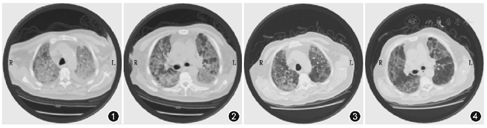

急诊检查:胸部CT(2020-2-16):两肺多发大片磨玻璃样密度影,内有小网格影,弥漫性间质病变,胸腔积液(图1,图2)。血气分析(吸纯氧)示:pH 7.370,cLac 9.1 mmol/L,PCO2 26.9 mmHg,PO2 192 mmHg,HCO3-15.6 mmol/L。血常规:白细胞14.24×109/L,红细胞4.58×1012/L,血红蛋白139g/L,血小板431×109/L,淋巴细胞0.053,中性粒细胞0.902,淋巴细胞绝对值0.76×109/L。生化示:GLU 12.78 mmol/L,CO2CP16.2mmol/L,K 5.6 mmol/L,Na130 mmol/L,Cl 90 mmol/L,BuN4.7 mmol/L,Cr 60 μmol/L。凝血功能:PT 17.1s,FIB 6.75 g/L。重症五项:CK-MB 7.5 ng/ml,cTnT0.16 ng/ml,MYO 122.4 ng/ml,BNP36.9 pg/ml,D-dimer>5 mg/L。入院心电图示:窦速。超声(床旁):EF59%左房增大,左室壁运动不协调,左室收缩功能正常,舒张功能减低。

诊疗方案:患者免疫力低下,基础病明确,重症肺炎,呼吸窘迫,感染面积大,入院给予美罗培南0.5 g,每8小时1次静脉滴注,甲基泼尼松龙40 mg、喘定0.5 g静脉滴注,持续无创呼吸机辅助通气治疗,辅以化痰、护胃等治疗。患者静息状态下无明显喘憋症状,无发热,无明显咳嗽,咳痰,逐渐给予脱无创呼吸机,继续抗炎治疗,于脱机后4 h、6 h、10 h、34 h、出院前复查血气分析,氧合指数检测分别是179、192、205、277、376,提示患者的限制性通气障功能、弥散功能较前逐渐改善。同时对急诊血常规白细胞14.24×109/L,中性粒细胞0.902,淋巴细胞绝对值0.76×109/L;入科时血常规白细胞16.12×109/L,中性粒细胞0.811,淋巴细胞绝对值2.37×109/L;入科48h血常规白细胞14.38×109/L,中性粒细胞0.839,淋巴细胞绝对值1.95×109/L;入科72h血常规白细胞9.27×109/L,中性粒细胞0.608,淋巴细胞绝对值2.99×109/L出院前血常规白细胞9.31×109/L,中性粒细胞百分数0.630,淋巴细胞绝对值2.76×109/L进行比较,提示感染逐渐减轻,淋巴细胞恢复正常。复查胸CT两肺多发大片状,片状磨玻璃密度影明显减少,两次胸腔积液较前明显吸收(图3,图4)。患者病情改善,于2020年3月3日出院。

首先,结合本病例患者否认流行病学,临床信息显得更重要。本例患者入院时病情危重,因喘憋加重伴发热入院,呼吸困难、紫绀、血临床氧饱和度50%,其中最难鉴别的辅助检查,胸部CT显示两肺多发大片磨玻璃样密度影,内有小网格影,弥漫性间质病变,胸腔积液,与新冠肺炎影像学改变类似[4]。新冠肺炎患者典型的CT表现为:早期呈单发或多发的斑片状磨玻璃影,伴有小叶间隔增厚;进展期表现为病灶增多、范围扩大,磨玻璃影与实变影或条索影共存;重症期表现为双肺弥漫性病变,少数呈"白肺"表现,以实变影为主,合并磨玻璃影,多伴条索影以及空气支气管征。疫情期间我们首先结合患者流行病学史、症状、体征、辅助检查,总结本例患者救诊发热门诊时病例特点,符合第五版新型冠状病毒感染的肺炎诊疗方案诊断标准。列入考虑新冠肺炎危重型疑似病例。

本例患者经过连续两次核酸检测阴性(间隔24 h),排除疑似新冠肺炎诊断,同时经无创通气、抗炎、甲泼尼龙静点后症状喘息改善,无发热,复查氧合指数较前好转,脱机时间延长,白细胞中性粒细胞及淋巴细胞绝对值恢复正常治疗有效。复查胸部CT双肺渗出影较前明显吸收,故排除COVID-19诊断。